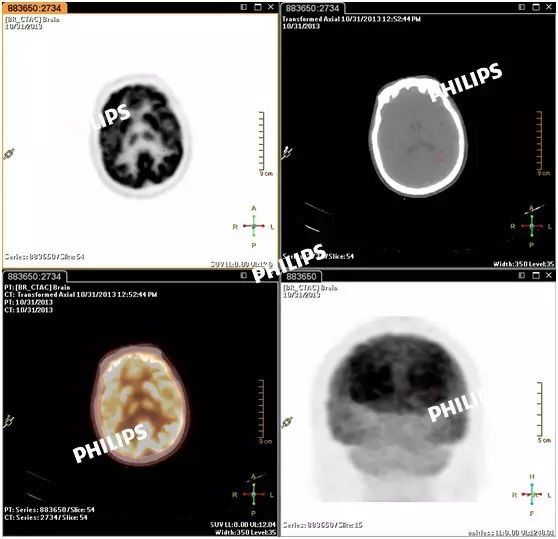

代入fusion viewer。此时会显示没有调整前的图像,如下图: